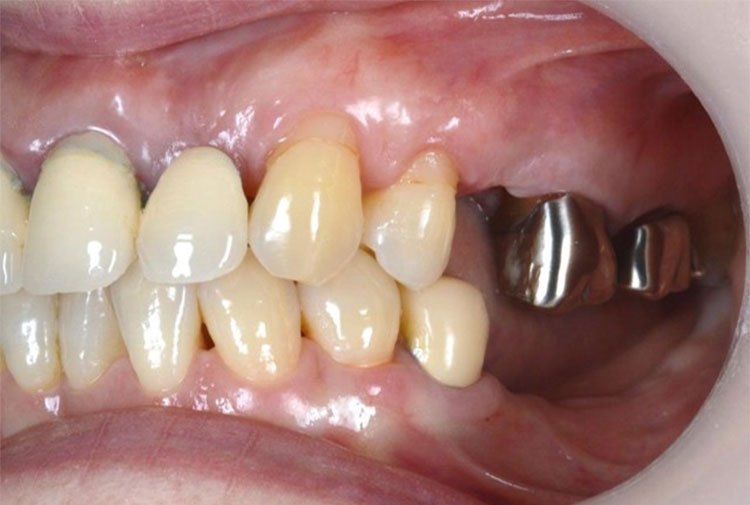

インプラント症例 Case3

Treatment cases

Before

After